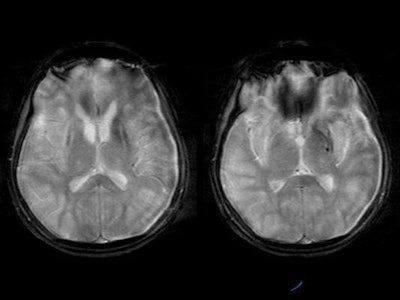

MRI was performed with the following sequences: TSE and gradient-echo T2 and FLAIR axial, TSE T2 sagittal and coronal, 3D Turboflash T1 sagittal with multiplanar reconstructions, and diffusion-weighted images with b-values of 500 and 1000 s/sq mm.

Diffuse hyperintensity at the cortex of both cerebral hemispheres on T2W and FLAIR images, with sparing of the white matter, was present [Figure 4]. These regions appeared mildly hypointense on T1WI. Mild sulcal effacement is seen in the involved regions.